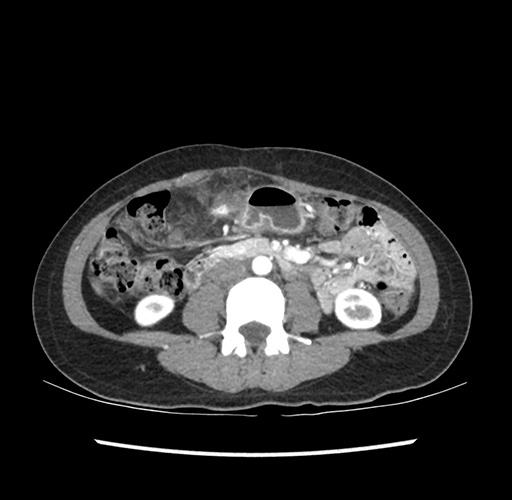

Imaging Analysis

Look through the patient's CT scan to identify any areas of concern for the necessary procedure.

Based on your CT findings, which issue(s) would give reason for "planned slowing down moment(s)" in this case?

Considering a standard left lateral sectionectomy procedure, what step(s) of the operation would you do differently in this case ?